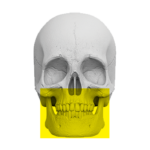

Zakres pracy tomografu.

(Badanie CBCT)

Szczęka i żuchwa

( 12 cm x 10 cm )

Staw skroniowo-żuchowy

+ zatoki szczękowe

( 16 cm x 10 cm )